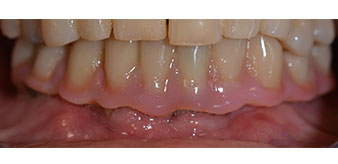

La paziente, 64 anni, presenta una dentatura residua di denti 38, 33 e 43 e una protesi combinata innestata nella mandibola (Fig. 1 e 2).